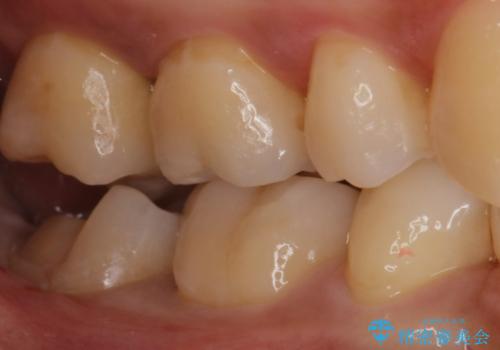

昔の被せ物が取れてしまった セラミックアンレーで治療

- 昔に治療した金属のかぶせものが取れてしまい来院されました。他院にて応急処置がされており、レントゲンなどで現状を把握した後、切削量が比較的少なく短期間で終了するセラミックアンレーにて治療いたしました。

経過良好で噛み合わせなども問題なく、前の被せ物より綺麗な被せ物がセットされ、非常に満足いただけました。